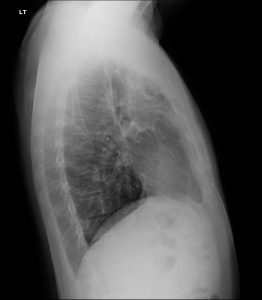

Fig. 2 Lateral view of the lungs